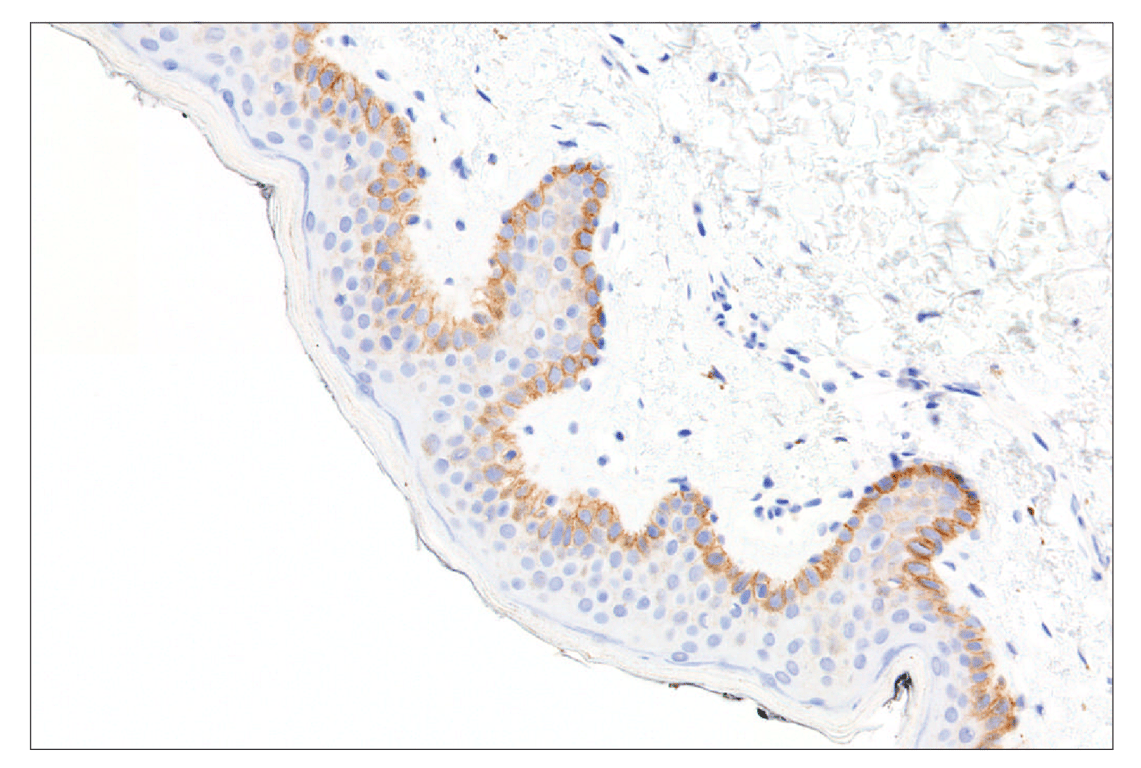

Immunohistochemical analysis of paraffin-embedded normal human skin using FGF Receptor 2IIIb (FPR2-D) Mouse mAb performed on the Leica BOND RX.

Immunohistochemistry Image 4: FGF Receptor 2IIIb (FPR2-D) Mouse Monoclonal Antibody